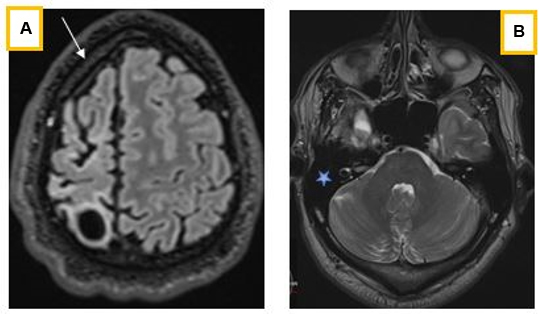

Radiologically, the cerebral hemispheres were asymmetrical, with reduced volume of the right hemisphere (Figure 1 and Figure 2), which was the site of a leukomalacia lesion with compensatory enlargement of the homolateral lateral ventricle (Figure 2). There was also widening of the homolateral cortical sulci, which was more marked opposite the leukomalacia focus, hyperpneumatization of the frontal sinuses (Figure 1) and calvarial thickening, predominantly on the lesion side (Figure 3A), but also of the mastoid cells, which had a compensatory appearance (Figure 3B). It was associated with discrete atrophy of the right cerebral peduncle (Figure 4A) and a reduction in homolateral hippocampal volume (Figure 4B).

Computed tomography (CT) imaging, especially magnetic resonance imaging (MRI), is theore essential for accurate diagnosis, assessment of severity and appropriate management [9],[10]. It classically describes cerebral hemiatrophy, usually accompanied by ipsilateral compensatory bone hypertrophy, such as thickening of the ipsilateral calvaria, hyperpneumatization of the frontal sinuses and mastoid cells, and elevation of the orbital roof and petrous ridge and contralateral hemiparesis [7],[11]. This asymmetry in the prominent development of the frontal sinus may be accompanied by an increase in the thickness of the diploe of the frontal bone on this side. It may be associated with mesencephalic and/or hippocampal atrophy [8], as was the case in our patient.